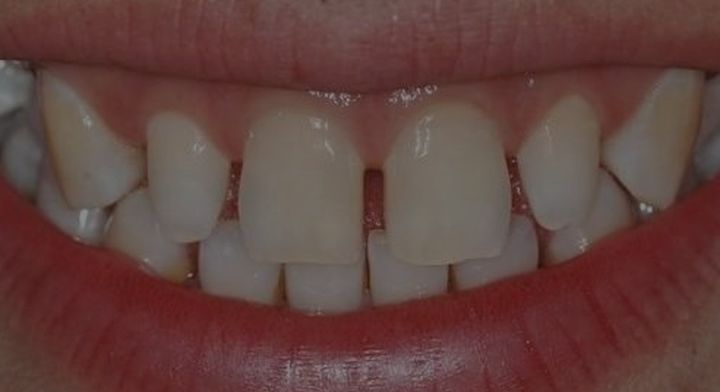

(如果牙齿缺损严重,做冠修复可以增加牙齿使用寿命)

既然全冠有诸多问题,那为什么医生还是建议患者做全冠?

那是因为,医生建议做全冠的牙齿,往往已经是坏得很严重的牙齿。比如牙髓炎,根管治疗,牙髓已经坏死后的牙齿,会慢慢变脆,一点一点碎掉,不做全冠,牙齿可能在使用半年一年后,就会因为咬硬物而碎掉,牙齿一旦咬碎了,可能就要面临拔除。

做了全冠,原本只能用一两年的坏牙,还可以苟且用个十年八年的,要是使用得当,用十年二十年也是有可能的。

所以做全冠的目的,是使残缺的牙齿,恢复牙齿的功能,延长牙齿的使用寿命。